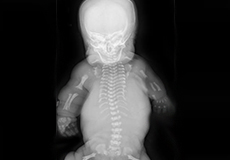

Spina Bifida

Spina bifida is a congenital condition (birth defect) in which there is abnormal development of the back bones, spinal cord, surrounding nerves, and the fluid-filled sac that surrounds the spinal cord.